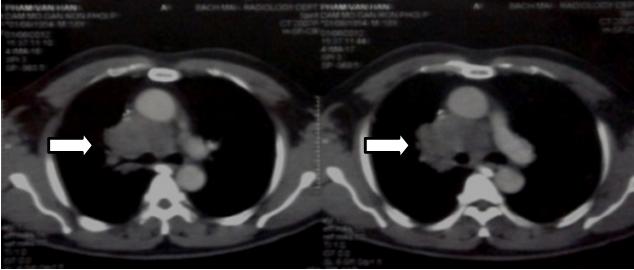

So sánh hình ảnh chụp CT ngực trước và sau điều trị

Hình 3: Chụp cắt lớp lồng ngực trước điều trị